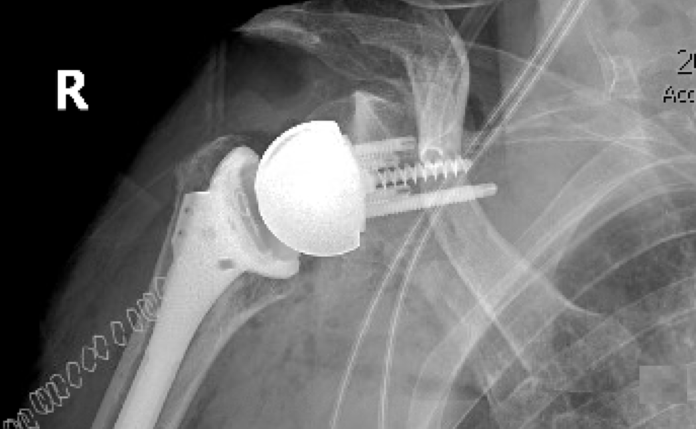

Place the baseplate flush with the inferior glenoid rim

Select and place humeral component to achieve a 135° liner-shaft angle

Target 4–10 mm of lateralization of the glenosphere center of rotation (CO): defined as the distance from the glenosphere center of rotation (COR) to the glenoid bone surface (includes the thickness of the baseplate, bone graft and/or augment). Know your glenospheres and don’t rely on the numbers on the box: for example, in one implant system the 3mm baseplate plus a “32-4” glenosphere lateralizes the center of rotation by 9mm.

Place baseplate in 0 – 10 degrees of inferior tilt: central screw parallel to floor of supraspinous fossa so that the humeral force on the glenosphere is perpendicular to the screw fixation.

Avoid excess humeral distalization: acromiohumeral interval (AHI) <30mm, humeral lengthening (pre to postoperative change in AHI) <20mm.

Global Lateralization (GL): distance from the glenoid bone surface to the lateral tip of the greater tuberosity (= GT + humeral component contribution). Includes the baseplate and augments. This is the distance that the tuberosity is lateralized from the native glenoid bone. Increases in GL tighten the shoulder – increasing stability, but may also increase the risk of contact between the tuberosity and the acromion when the arm is elevated.

Effective Glenosphere Thickness (GT): distance from the glenoid bone surface to the lateral edge of the glenosphere (= CO + glenosphere radius). Includes the baseplate and augments. This is the glenosphere contribution to global lateralization

Center of Rotation Offset (CO): distance from the glenoid bone surface to the glenosphere center of rotation (COR). Includes the baseplate and augments. The COR is the pivot point around which the tuberosity rotates. The position of the COR defines the moment arm for deltoid action.